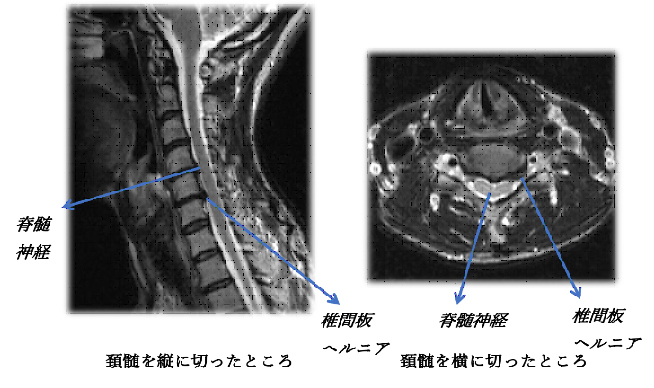

脊髄・脊椎疾患 | 名古屋大学大学院医学系研究科 脳神経外科学, 頚椎脊柱管狭窄症の症例と症状について|白石脊椎クリニック,

頚椎脊柱管狭窄症の症例と症状について|白石脊椎クリニック, 脊椎脊髄センター | 総合東京病院【公式】中野区 練馬区 24時間,